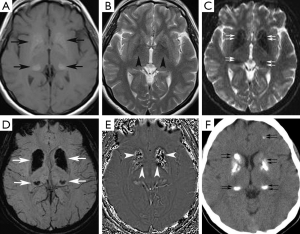

A 37-year-old woman presented at our neurology outpatient clinic with headache, vertigo, ataxia, tremor, and confusion without loss of consciousness 2 days ago. Neurological examination showed postural kinetic tremor. Cranial MRI revealed symmetrical hyperintense signal mostly in the basal ganglia and bilateral thalami, also involving less prominently periventricular white matter and bilateral dentate nuclei on T1-weighted images (Figure 3A). T2-weighted images showed mild hypointense signal changes in the basal ganglia (Figure 3B). These signal changes were hypointense on GE images (Figure 3C), SWI minIP (Figure 3D) and phase images (Figure 3E), consistent with calcification. Brain CT imaging confirmed calcifications (Figure 3F). EEG was normal. Calcium metabolism abnormalities were excluded by laboratory tests. The final diagnosis was FD.